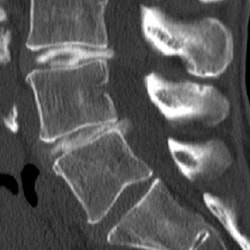

The upper X-ray image shows a discography of a herniated disc with a leakage of a contrast agent into the spinal canal (lower disc). The contrast agent is injected through fine needles. It is visible as a dark/black fluid. The lower CT image shows a reconstructed spine for the better evaluation of even small tears of a vertebral disc. The contrast agent is visible as a bright/white liquid.